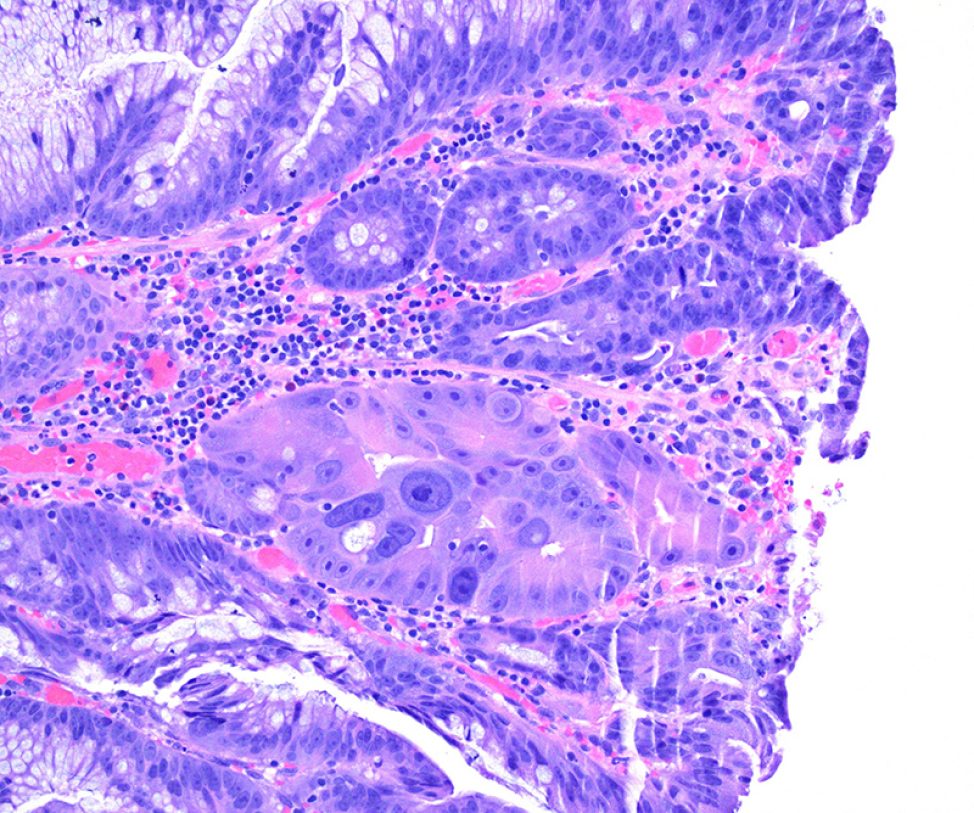

As a proof of principle, our lab recently demonstrated that modulation of a colonic mucosa-relevant growth factor alone could lead to emergence of neoplasia-associated phenotypes in non-transformed organoids. Epidermal growth factor (EGF) is a critical mitogen in the intestinal stem cell niche. Normal colon epithelial organoids (colonoids) typically require EGF for survival, whereas colorectal cancer organoids with KRAS or PIK3CA alterations grow independently of EGF. We showed that normal and colitis-derived colonoids adapted to EGF-independent growth over the course of many months exhibited chromosomal instability, cytologic features of dysplasia, and colorectal cancer-associated transcriptional reprogramming. Further, colitis-derived colonoids had accelerated adaptive potential in our model. Our lab continues to investigate the lasting molecular impact of perturbations to niche homeostasis on epithelial biology, specifically focusing on inflammatory bowel disease-associated dysplasia and sporadic early onset colorectal cancer.

Optically cleared normal human colonic mucosa